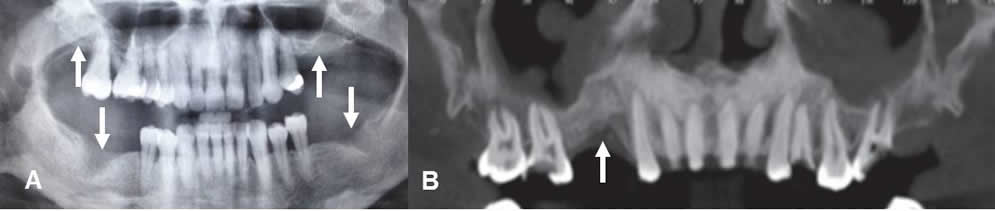

El objetivo principal del estudio preoperatorio por imágenes, es determinar si existe la suficiente cantidad de hueso alveolar, para colocar el implante. Otros son, conocer la exacta localización del canal mandibular y el foramen incisivo, para evitar su lesión durante la cirugía, saber las características de los senos maxilares y determinar las contraindicaciones o patologías asociadas. (Fig 17, 18, 19 y 20). (5, 3, 13).

El trauma del nervio alveolar inferior, ocasiona parestesias en la cara y la perforación del seno maxilar, aumenta la probabilidad de infección o falla del implante. (5, 13).

Fig 19. Patología asociada.

A: Dentascan reconstrucción coronal. Pérdida de piezas en ambas arcadas maxilares. Se aprecia engrosamiento en la mucosa de ambos senos maxilares, por sinusopatía, que debe ser tratada antes de colocar el implante.

B: TAC reconstrucción transversal. Sinusopatía maxilar, asociada a gran atrofia ósea.

Fig 20 A. Raíz retenida.

A: TAC axial, B: TAC reconstrucción panorámica y C: TAC sagital.

Ausencia de piezas, en el lado izquierdo del maxilar, con fragmento de raíz retenida.

Fig 20 B. Raíces retenidas.

A y B: TAC reconstrucción panorámica y C: TAC reconstrucción coronal.

Ausencia de molares y premolares a nivel bilateral, con fragmentos de raíces retenidas.

La proyección panorámica u ortopantomografía, es la modalidad mas usada en el estudio preoperatorio de los implantes dentales. (10). Es simple y barata, pero proporciona información insuficiente. Genera distorsión geométrica en el 25% de los casos, por la superposición de estructuras. (2, 7, 10). (Fig 20 C).

Fig 20 C. Ortopantomografía normal

Ausencia de varias piezas dentales. También hay implantes colocados, en el lado derecho del maxilar y el izquierdo de la mandíbula.